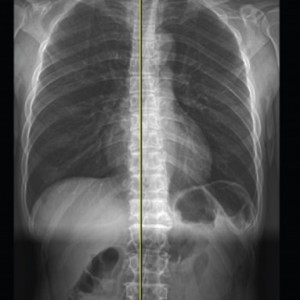

연산당당한방병원

Before & After

해당 사진은 수정없는 실제 치료사진입니다.

환자의 치료결과는 환자의 상태, 치료방법 등에 따라 차이가 발생할 수 있습니다.